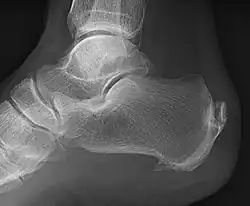

A radiograph showing osteophytes on the posterior and inferior aspects of the calcaneus

A calcaneal spur (also known as a heel spur) is a bony outgrowth from the calcaneal tuberosity (heel bone).[1] Calcaneal spurs are typically detected by x-ray examination.[2] It is a form of exostosis.

An inferior calcaneal spur is located on the inferior aspect of the calcaneus and is typically a response to plantar fasciitis over a period, but may also be associated with ankylosing spondylitis (typically in children). A posterior calcaneal spur develops on the back of the heel at the insertion of the Achilles tendon.[3]

An inferior calcaneal spur consists of a calcification of the calcaneus, which lies superior to the plantar fascia at the insertion of the plantar fascia. A posterior calcaneal spur is often large and palpable through the skin and may need to be removed as part of the treatment of insertional Achilles tendonitis.[3]